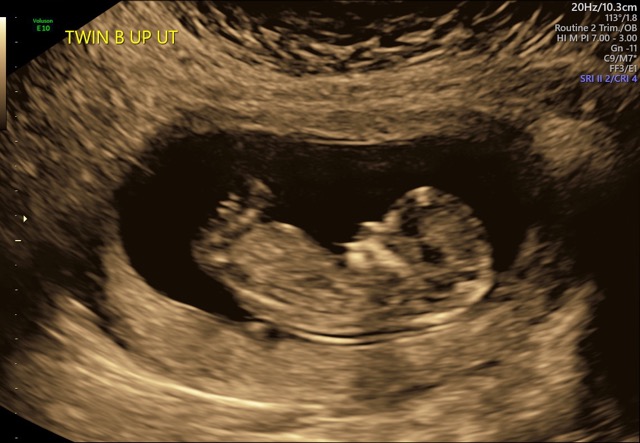

July 2020 Di/Di twins

This is my first pregnancy, I’m 13 weeks with Didi twins and were super excited. I do have a large cyst that could potentially cost me to lose an ovary but they said as long as it stays put I should be fine, that’s my main concern but I got to see them at the Nuchal exam yesterday and they’re starting to look like actual babies!! I’m due the end of July this year and hoping for boy/girl twins! Mainly just praying that they’ll both be healthy and stay out until then. Any guesses on the genders?! I just did the Harmony test today so we should be finding out within the next week or so☺️